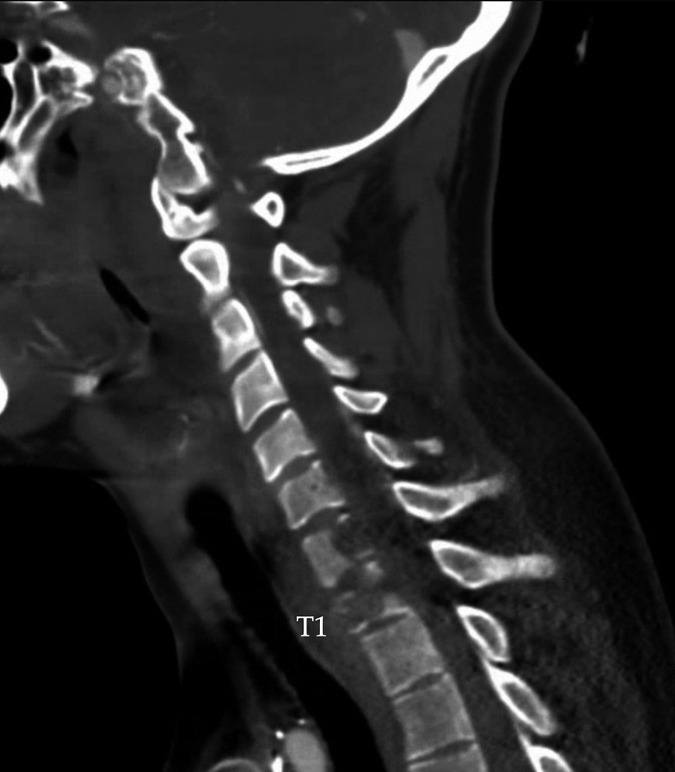

Case description: A 28-year-old male with a history of YST presented to our institution with urinary retention, increasing weakness in the upper extremities, and acute onset lower extremity weakness. Computed tomography (CT) and magnetic resonance imaging (MRI) scans confirmed evidence of metastasis from a known YST with symptomatic cord compression. The patient was treated with surgical excision via decompressive laminectomies with instrumentation as described, and histopathologic analysis of the specimen confirmed YST metastasis. His disease recurred one year after index surgery. He succumbed to his disease despite repeated debulking.